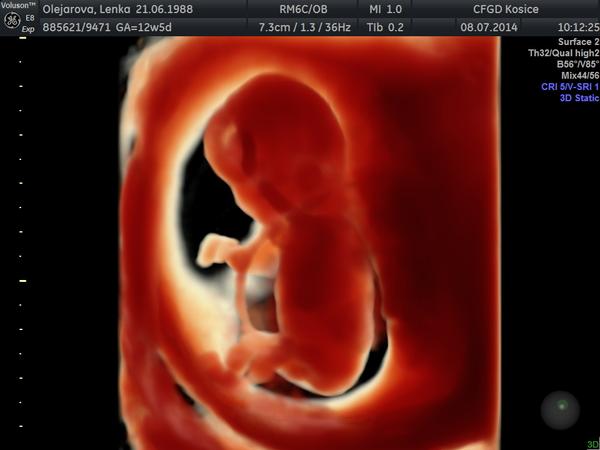

Krasne ranko bambulky, tak z nasho ducha krasneho tu mame uz podla utz 14 tt 🙂 Vcerajsie NT meranie dopadlo na jednotku, podla lekara je to chlap ako lusk, ale 1. augusta ma objednal znova na sono a na tripple testy tak povedal, ze uz to len potvrdi 🙂 teraz to bolo tak na 90 percent , ale trcalo tam cosi 🙂 pupocnik to nebol, lebo ho ma drobuliatko okolo krku 🙂 Vsetky vysledocky mame super a sme vacsi o 2 dni 🙂 tesime sa. vsetkym snazilkam drzime palusky :* drzte sa.